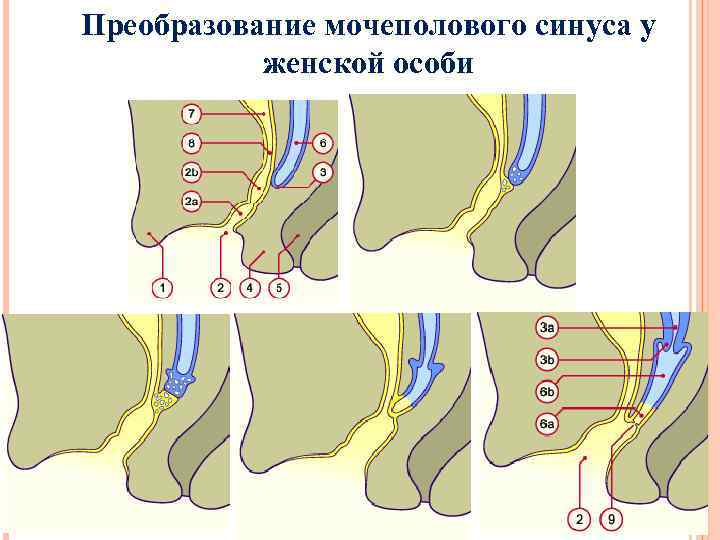

Преобразование мочеполового синуса у женской особи

Преобразование мочеполового синуса у женской особи